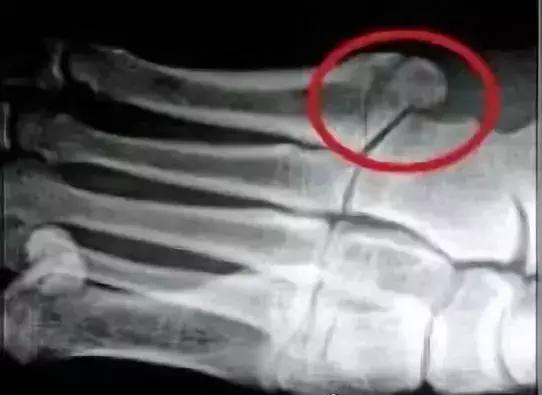

2.琼斯骨折

琼斯骨折是骨科和运动医学棘手的一种的运动伤害,不只是足球员,任何人都有可能发生。跖骨是足部的一块小骨头,而琼斯骨折就是发生在第五跖骨的基底部,为一种横向骨折,意思是骨折线是垂直于跖骨骨干的,它是由于腓股短肌的肌腱过度用力拉扯所引起的撕脱性骨折。

这样的伤害问题虽小,但也十分棘手。因为骨折位置是第五跖骨上,而这部分的血液循环较少,在加上这里容易发生骨头愈合不佳,所以治疗恢复上会比其他撕裂骨折要来的更难治疗。

所以对于患有琼斯骨折的人面临着更困难的挑战,这种骨折很难在没有手术的情况下愈合。由于运动员有较大的运动伤害风险,所以骨科医师通常选择手术修复骨折。

手术通常包括在骨折内放置螺钉。如果试图进行非手术治疗,例如打石膏,那么就必须使用X光做密切的观察。